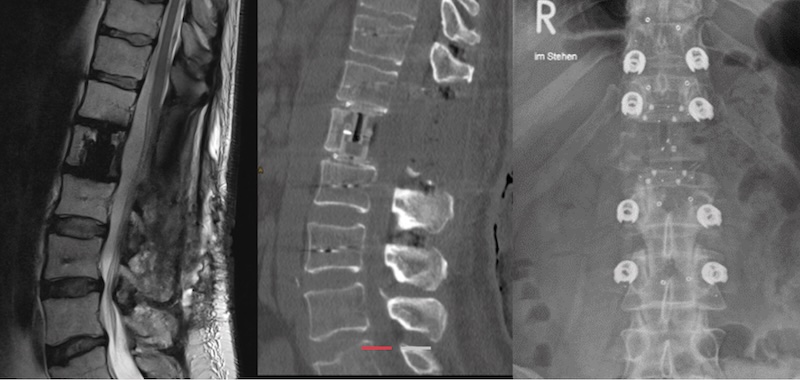

The KONG -TL VBR System by icotec Medical is an expandable corpectomy spacer composed of radiolucent carbon fiber and PEEK materail that features titanium coated endplates for increased bony integration. The KONG -TL is intended for use in the thoracolumbar spine and features modular endplates of various sizes, shapes and lordosis options. Endplates are secured via a carbon-fiber/PEEK screw

• Indicated for use in tumor cases of the spine